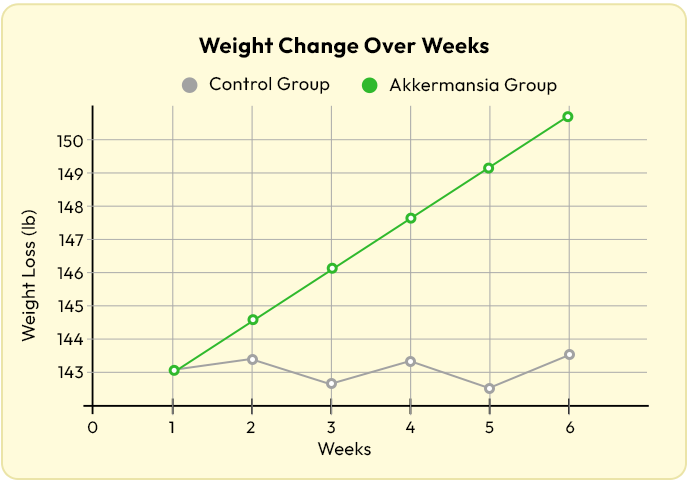

A brand-new 2024 clinical trial showed that participants taking potato starch…

Lost TWICE as much weight than those on a placebo.

Without changing their diet or exercise.

They lost over half a pound per week...

Consistently...

Just by adding this one compound.

A 2024 meta-analysis looked at 32 studies with over 1,100 people.

The results were just as shocking.

People who added chicory root lost 300% more belly fat than those who didn't.

Even when their diets stayed exactly the same.

It also helped lower the hunger hormone ghrelin by up to 40%.

Meaning people ate less...

- Without even thinking about it.

- Without restriction.

- And without rebound.

And the longer they took it...

The better the results.

One human study showed that people taking Akkermansia lost over 5 pounds in just a few weeks.

Without changing anything else.